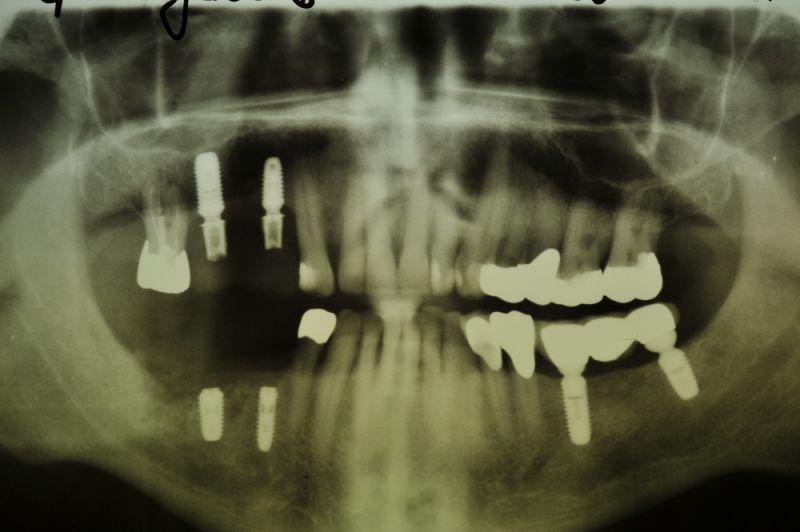

Vor ca. 20 Jahren wurde der Patient umfassend funktionstherapeutisch versorgt. Bereits zum damaligen Zeitpunkt waren die Zähne des Patienten vorgeschädigt und es lag eine Parodontalerkrankung vor.

Der Patient wurde dann über etliche Jahre, was das Thema Parodontalrecall betrifft nicht ganz optimal betreut, weil die berufliche Situation des Patienten das nicht zuließ.

In der Zwischenzeit sind vorgeschädigte Zähne verloren gegangen und wurden zum Teil durch Implantate ersetzt.

Über eine mehrjährige Phase wurden immer wieder Laborgefertigte Dauerprovisorien eingegliedert, weil vor einer abschließenden funktionstherapeutioschen Behandlung erst noch andere Problemzonen beseitigt werden mussten.